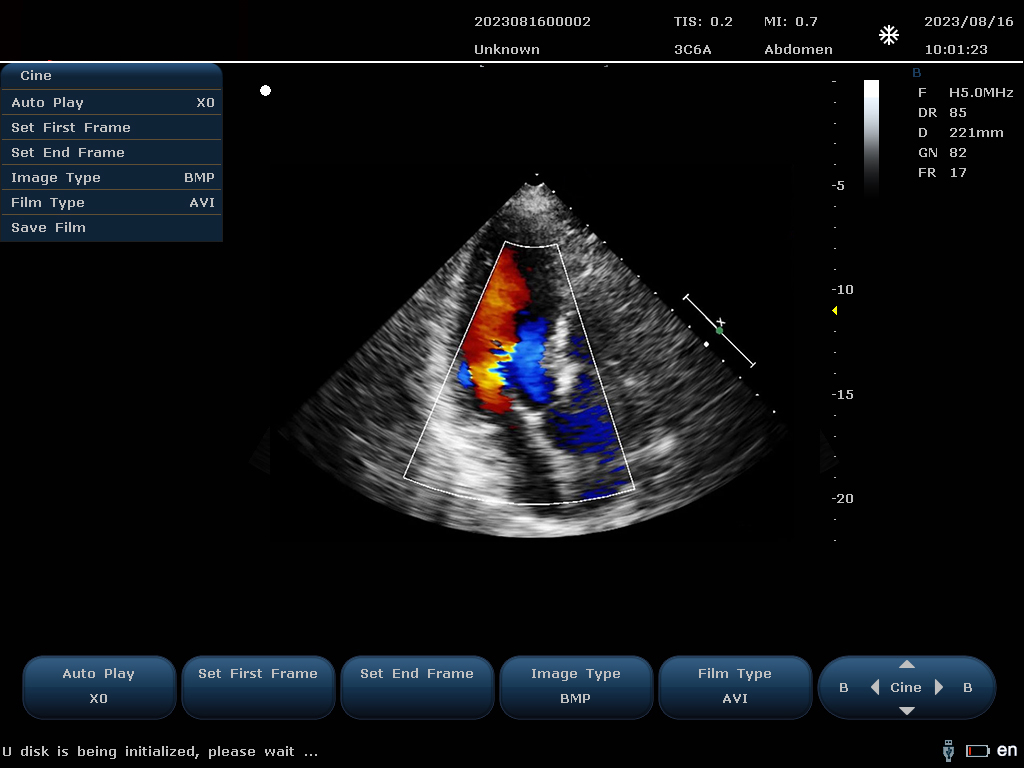

設備通過檢測這些頻移信號,并利用復雜的信號處理技術,包括傅立葉變換等,分析血流的方向、速度和分布。彩色編碼后,血流信息被疊加在傳統的黑白超聲二維圖像上,形成彩色多普勒圖像,直觀顯示血流動態。

最終,這些信息轉化為圖像顯示在屏幕上,醫生可以根據圖像中血流的顏色(通常紅色代表血流朝向探頭,藍色代表遠離探頭)和亮度來判斷血流的性質和異常情況,如血流速度增快可能指示狹窄,無血流區域可能意味著阻塞等。